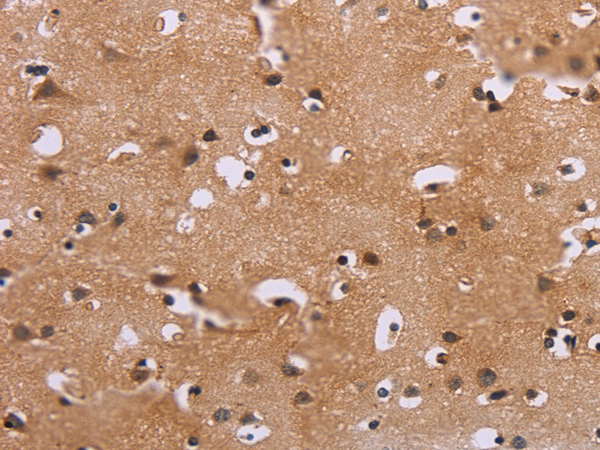

IHC positive control: |

Human breast cancer |

IHC Recommend dilution: |

5-20 |